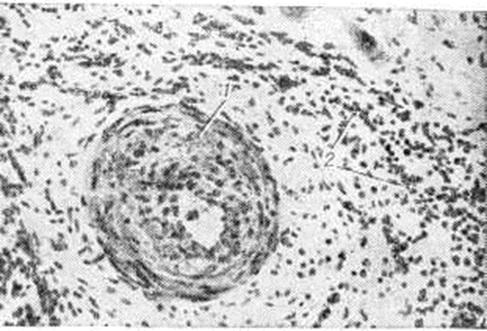

Рис. 6.

Микропрепарат миокарда при плазмоцитарном миокардите: видны плазматические клетки (1), располагающиеся в фиброзной ткани (2); × 400.

Рис. 7.

Микропрепарат миокарда при подостром септическом миокардите: склероз интрамиокардиальной артерии (1) с резкой облитерацией её просвета, периваскулярный склероз и воспалительная инфильтрация (2); × 100.

Экссудативный компонент представлен жидкой частью крови и её форменными элементами в различных соотношениях. Преобладание серозного экссудата с небольшим количеством лейкоцитов приводит к развитию острого серозного Миокардит, встречающегося при токсико-инфекционных поражениях миокарда различной этиологии. При этом пучки мышечных волокон раздвинуты серозным экссудатом, содержащим небольшое количество клеток крови, чаще всего — сегментоядерные лейкоциты. Наблюдаются случаи экссудативного Миокардит с преобладанием эозинофилов в экссудате и инфильтратах. Эозинофильный Миокардит нередко является частью синдрома Леффлера и сопровождается эозинофилией и эозинофильной инфильтрацией органов — лёгких, селезёнки и другие (смотри полный свод знаний Леффлера синдром). К клеткам экссудата иногда присоединяются клетки лимфогистиоцитарного инфильтрата из межуточной ткани сердца. Клетки инфильтрата частично трансформируются в клетки плазмоцитарного ряда, и иногда инфильтрат состоит (в основном) из плазматических клеток (смотри полный свод знаний); в этих случаях можно говорить о плазмоцитарном Миокардит (рисунок 6). При длительном течении Миокардит нарастают процессы фиброплазии за счёт размножения фибробластов межуточной ткани сердца и фиброцитарного превращения гистиоцитов. В результате очаг воспаления замещается рубцовой тканью и развивается миокардитический кардиосклероз.

Обычно при Миокардит выявляются изменения внутримиокардиальных кровеносных сосудов по типу гиперергического васкулита. Обнаруживаются все стадии васкулита — от фибриноидного некроза до склероза сосудистой стенки с частичной или полной облитерацией просвета сосуда (рисунок 7). Последовательность, при которой пролиферативные процессы следуют за начальными экссудативными, вовсе не является обязательной схемой. Лимфогистиоцитарная инфильтрация может развиваться с первых моментов воспалительной реакции, которая течёт по типу острого пролиферативного воспаления. Как видно из изложенного, при неспецифическом Миокардит отсутствует какая-либо специфика, позволяющая судить об его этиологии. Неспецифическими являются многие Миокардит при инфекционные заболеваниях, тонзиллогенный, лекарственный, поствакцинальный Миокардит, а также Миокардит при миастении, миокардит Абрамова—Фидлера.